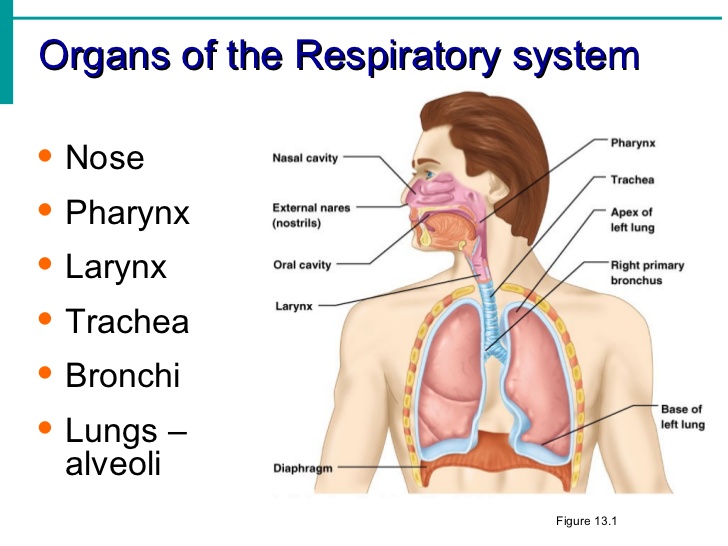

TOPIC: THE RESPIRATORY SYSTEM (HUMAN)

OBJECTIVE: At the end of the lesson, the students should be able to:

1. Define respiration.

2. Mention parts of the human respiratory system.

3. Differentiate between pharynx and larynx.

CONTENT:

Respiration is the process by which food substances are broken down in our body to release the energy we need.

The body does not depend on food alone for the production of all the energy required. There is the need for oxygen, which we get from the air we breathe in to break down food substances in our body releasing energy and some waste products.

PARTS OF THE HUMAN RESPIRATORY SYSTEM

The human respiratory system consists of a number of organs which work together to ensure the supply of oxygen to the body cells and the removal of carbon (IV) oxide from the cells.

These organs are:

(1 ) nostrils (2) larynx (3) pharynx (4) trachea (wind pipe) (5) bronchi (6) lungs (7 ) bronchioles (8) alveoli (9) mouth

(1) Nostrils:

Air enters the body through the nostrils which are lined with a membrane of cells that secrets mucus which moistens the air we breathe.

(2) Pharynx:

The nostrils lead into the pharynx which is the lower end of the mouth cavity.

(3) Larynx:

The pharynx leads into the larynx which is also called the voice box. The larynx leads into the trachea, which is also called the wind pipe.

(4) Bronchi:

The trachea leads into the bronchi, each bronchus leads into a lung.

(5) Lungs: each bronchus leads into a lung. Inside the lungs are tiny tubes called bronchioles. The bronchioles branch again into alveoli.